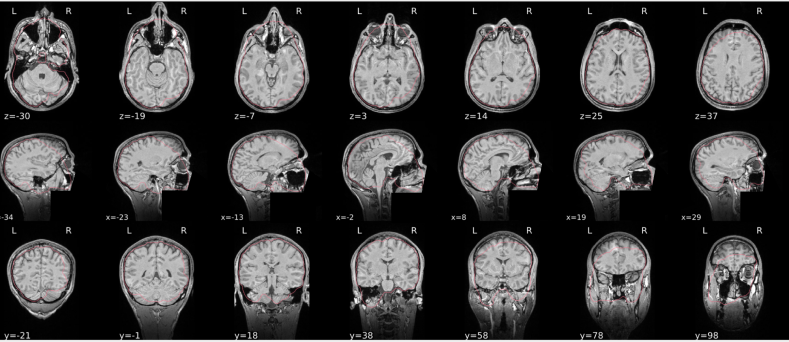

T1w skull stripping

Skull stripping is the process separating the brain (cortex and cerebellum) from the skull. The red line follows the outline of the brain and it separates it from the skull.

Example of a good subject

- There are no skull stripping errors, such as portions of the brain missing, or too much of the skull retained

- The red line follows the outline of the brain

Example of a bad subject

- There are skull stripping errors, such as portions of the brain missing, or too much of the skull retained

- NOTE: check all the images (slices) in the report. If only one image (slice) looks problematic, it is possible that the subject is okay and it is just a visual issue in that particular screenshot

Summary

| Good | Bad |

|---|---|

| The brain is fully inside the red line | Structures like the cranium or the eyes are inside the red line |

| No important brain structures are outside of the red line red line follows the natural outline of the brain | Important brain structures are missing inside of the red line |

-> if only one slice is problematic, it could be an issue related to the visual depiction of the data instead of an issue related to the test subject